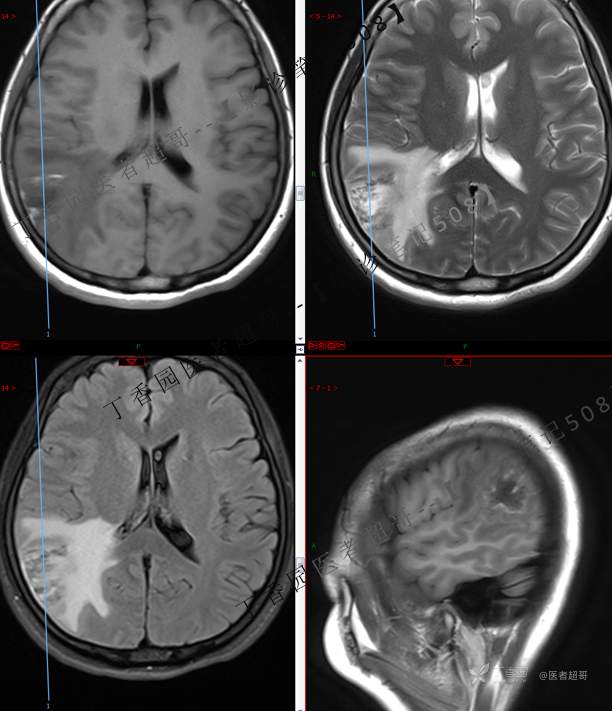

【影诊笔记508】同病异影,个人感觉有难度,欢迎分析,领丁当!有详细术程及病理!

主 诉:突发一过性意识不清伴肢体抽搐5天余。

现病史:患者5天余前无明显原因及诱因出现一过性意识不清,伴肢体抽搐,持续约2-3分钟,后意识逐渐恢复,无明显头痛头晕,无恶心呕吐,无肢体抽搐,无呼吸困难,无二便失禁,后就诊于当地医院,行颅脑CT示“颅内占位性病变”,予以药物对症治疗,具体不详,门诊以“颅内占位性病变”,收入我科。患者自发病以来,未进饮食,近期体重无明显变化。